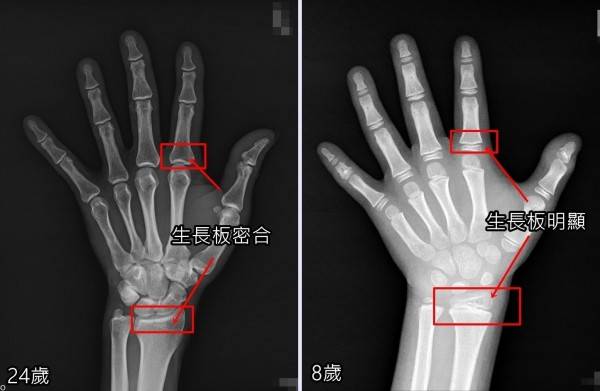

康程中醫診所 生長板 骨骺線 閉合 是骨骼正常發育的一個過程 骨骺與乾骺端之間的軟骨 在小朋友的手部x光片上表現為 Facebook

家长们知道吗 骨骺线 泄露长高秘密

年龄和骨龄 判断孩子的身高该看哪个

年龄和骨龄 判断孩子的身高究竟该看哪个